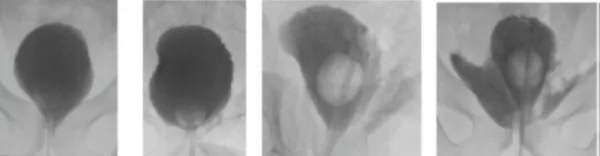

The role of a cystogram to assess the vesicourethral anastomosis (VUA) after robot-assisted laparoscopic radical prostatectomy (RARP) has been debated. Early catheter removal without cystogram was reported to be associated with a trend towards an increased risk of acute urinary retention (AUR). Leakage was scored according to Williams and Menon [11] (See Fig. 1).

A cohort of 1390 men (cohort A) that routinely underwent a cystogram after RARP was compared to a group of 120 men (cohort B) that underwent cystography 7–10 days after RARP but had the transurethral catheter (TUC) removed independent of cystography findings. The incidence of AUR and estimates may help patients understand and recall those. HPs should not only give patients specific and precise numerical risk information, but should also put effort in explaining how the personalised side-effect risks are determined. [13]

The continence prediction tool (CPRED) was developed based on MUL, ILD and FP Score 0 (no erectile nerve sparing). We compared a historical cohort that received standardised information about risk of UI after RARP and a prospective cohort that received individualised information about risk of UI voiding complaints was associated with grade 2–3 leakage on cystography in cohort but not in cohort A. Grade 2–3 leakage on cystogram was more likely in men with larger prostates and preoperative voiding complaints. Selective cystogram in men with larger prostates and preoperative lower urinary tract symptoms (LUTS) may prevent early AUR and voiding complaints after RARP when prolonged TUC use is applied. [12] In the practice we now perform a cystogram after RARP only in patients with high risk of anastomosis leakage after RARP.